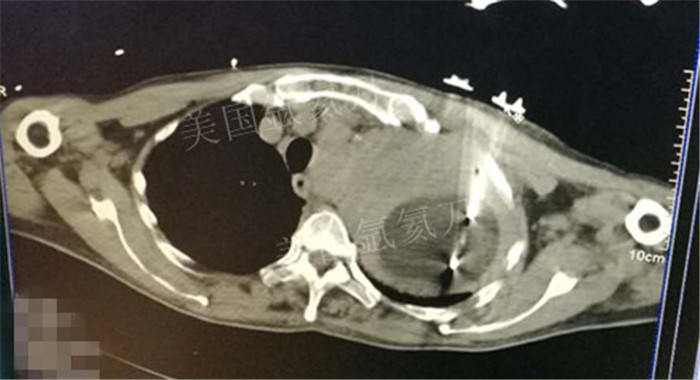

上一篇:煤炭总医院氩氦刀冷冻消融治疗双肺转移病灶

下一篇:氩氦冷冻治疗最大径8.2肿瘤,冰球最大径7.9